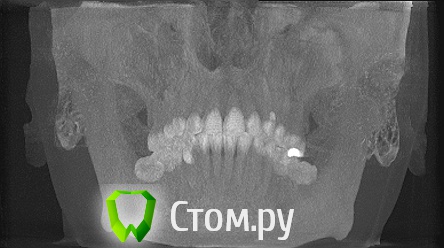

Дарья87 Опубликовано 13 мая, 2014 Автор Поделиться Опубликовано 13 мая, 2014 Еще есть снимки может кто то что то сможет прояснить.Возможно здесь есть хороший специалист.Нуждаюсь в совете.За раннее спасибо! Ссылка на комментарий

Дарья87 Опубликовано 13 мая, 2014 Автор Поделиться Опубликовано 13 мая, 2014 Восьмой зуб который на снимке его уже нет.Удалила так как он не мог выйти на поверхность и встать в зубной ряд Ссылка на комментарий